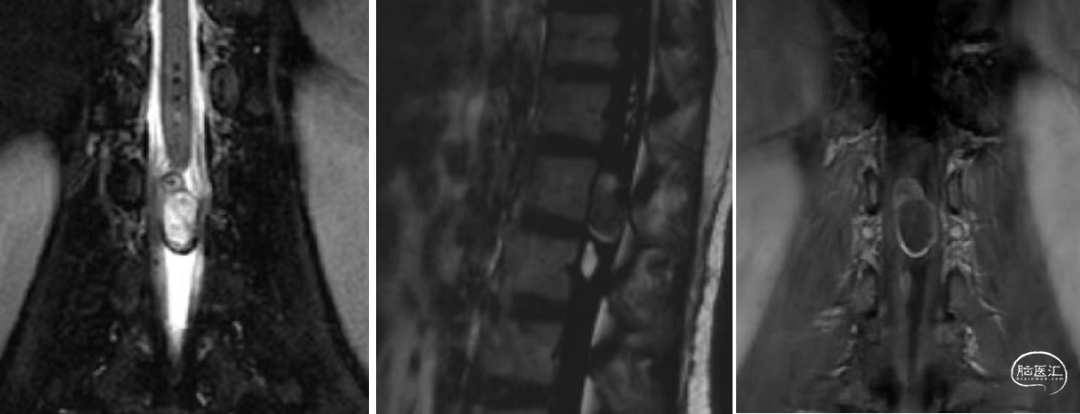

辅助检查:腰椎CT和MR示:L1-2椎管内硬膜下见一软组织信号结节,大小约24mm×12mm×10mm,T1W1低信号,T2W1稍高信号,增强扫描明显强化,但欠均匀,临近脊髓受压改变等。

术前腰椎CT和MR如下: